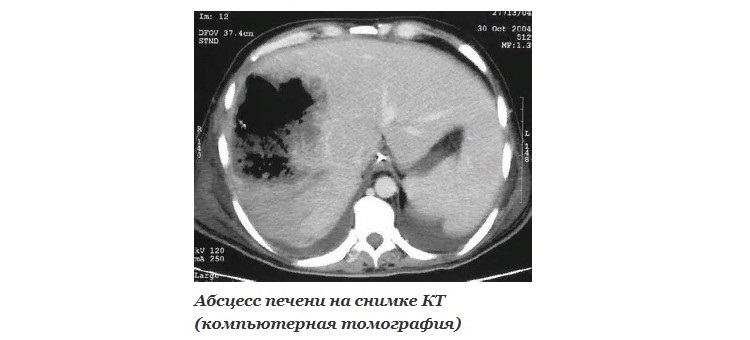

КТ, МРТ

Компьютерная и магнитно-резонансная томография – современные методы визуализации, часто использующиеся для диагностики поражений органов брюшной полости. Снимки позволяют выявить повреждения даже глубоких слоев ткани.

Очагово-деструктивные образования в виде гнойных полостей в печени очень хорошо видны на томограммах. Это дает возможность максимально точно диагностировать патологию и подготовиться к хирургическим манипуляциям.